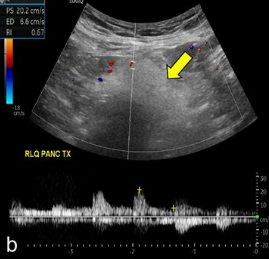

Evaluate the arterial flow of this transplant pancreas.

Arterial Doppler shows a sharp systolic upstroke with continuous diastolic flow and normal RI of 0.7. Findings suggest no complications.